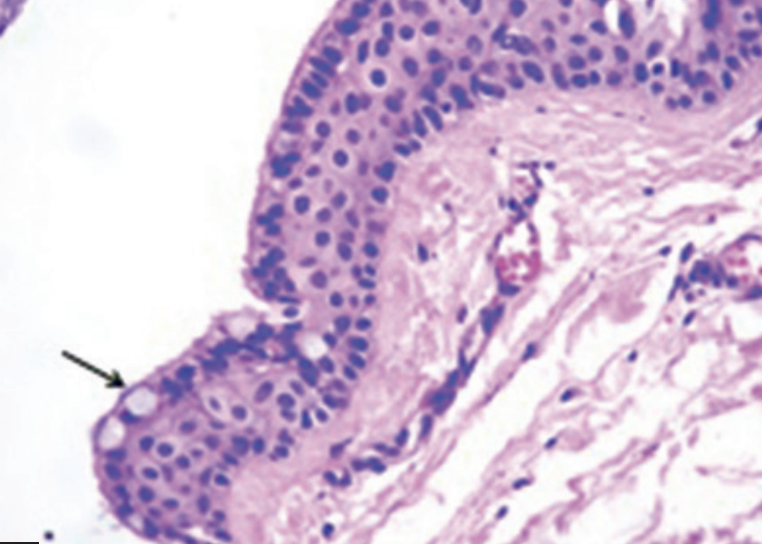

玻片特徵

- Developmental cyst

- epithelial lining 與結締組織交界處平整

- 非發炎型(noninflamed)

- 結締組織鬆散

- 糖胺聚醣基質(glycosaminoglycan ground substance)。

- 發炎型(inflamed)

- 網嵴(rete ridges)

- cholesterol clefts

- 齒源 → Rushton bodies

- true cyst

- 兩到四層的扁平非角化上皮

- Rushton bodies